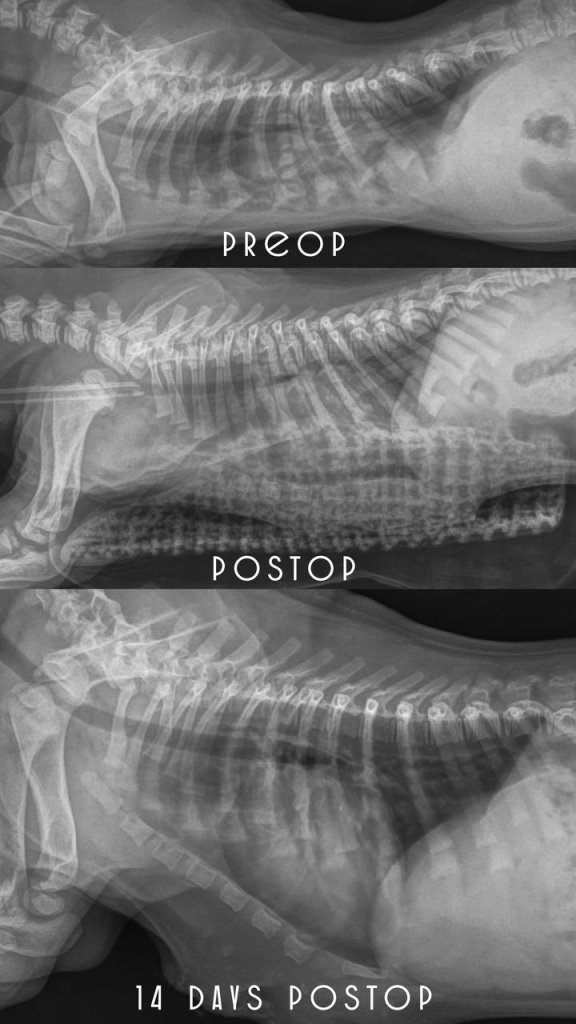

PECTUS EXCAVATUM

результат лечения

спустя 2 недели после операции

По рентгену — грудина как у здорового пациента 👍